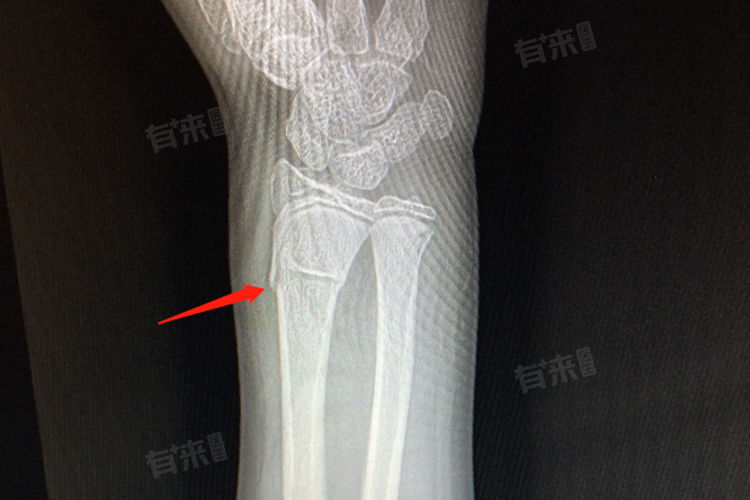

3、X线检查:作为诊断青枝骨折的主要手段,X线平片可清晰显示骨骼形态,发现骨皮质皱褶、隆起或部分断裂等特征性表现,明确骨折部位、类型及移位情况,为治疗方案制定提供关键影像资料。